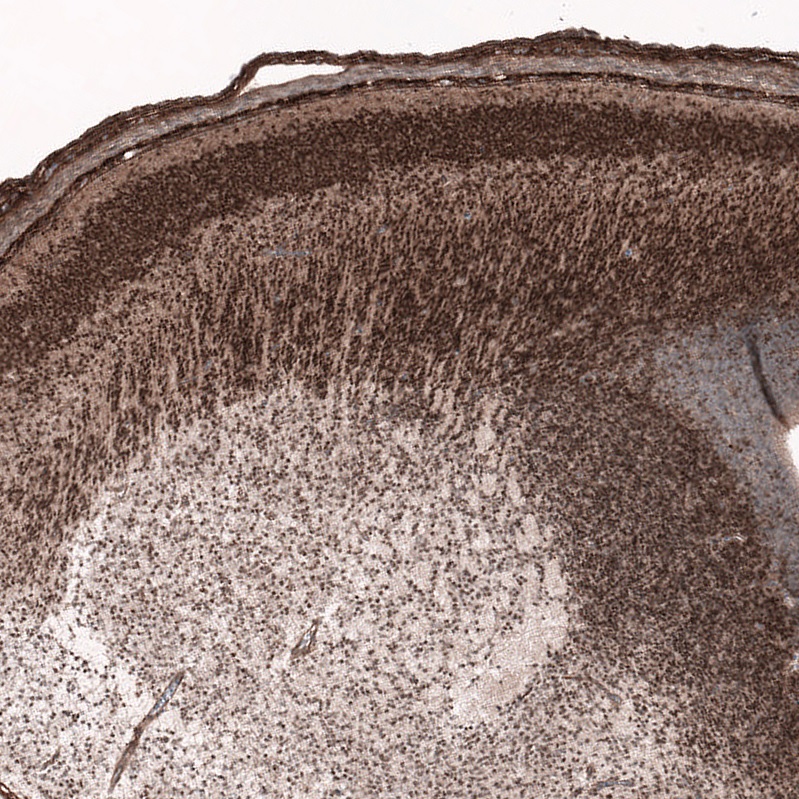

Immunohistochemistry (Formalin/PFA-fixed paraffin-embedded sections) - Anti-SOX11 antibody [EPR20457] - BSA and Azide free (AB239787)

Immunohistochemical analysis of paraffin-embedded human glioma tissue labeling SOX11 with ab229185 at 1/250 dilution, followed by Goat Anti-Rabbit IgG H&L (HRP) Ready to use. Nucleus staining on human glioma (PMID : 15583815.) is observed. Counterstained with hematoxylin.

Secondary antibody only control : Used PBS instead of primary antibody, secondary antibody is Goat Anti-Rabbit IgG H&L (HRP) Ready to use.

Heat mediated antigen retrieval using ab93684 (Tris/EDTA buffer, pH 9.0).

This data was developed using the same antibody clone in a different buffer formulation containing PBS, BSA, glycerol, and sodium azide (ab229185).